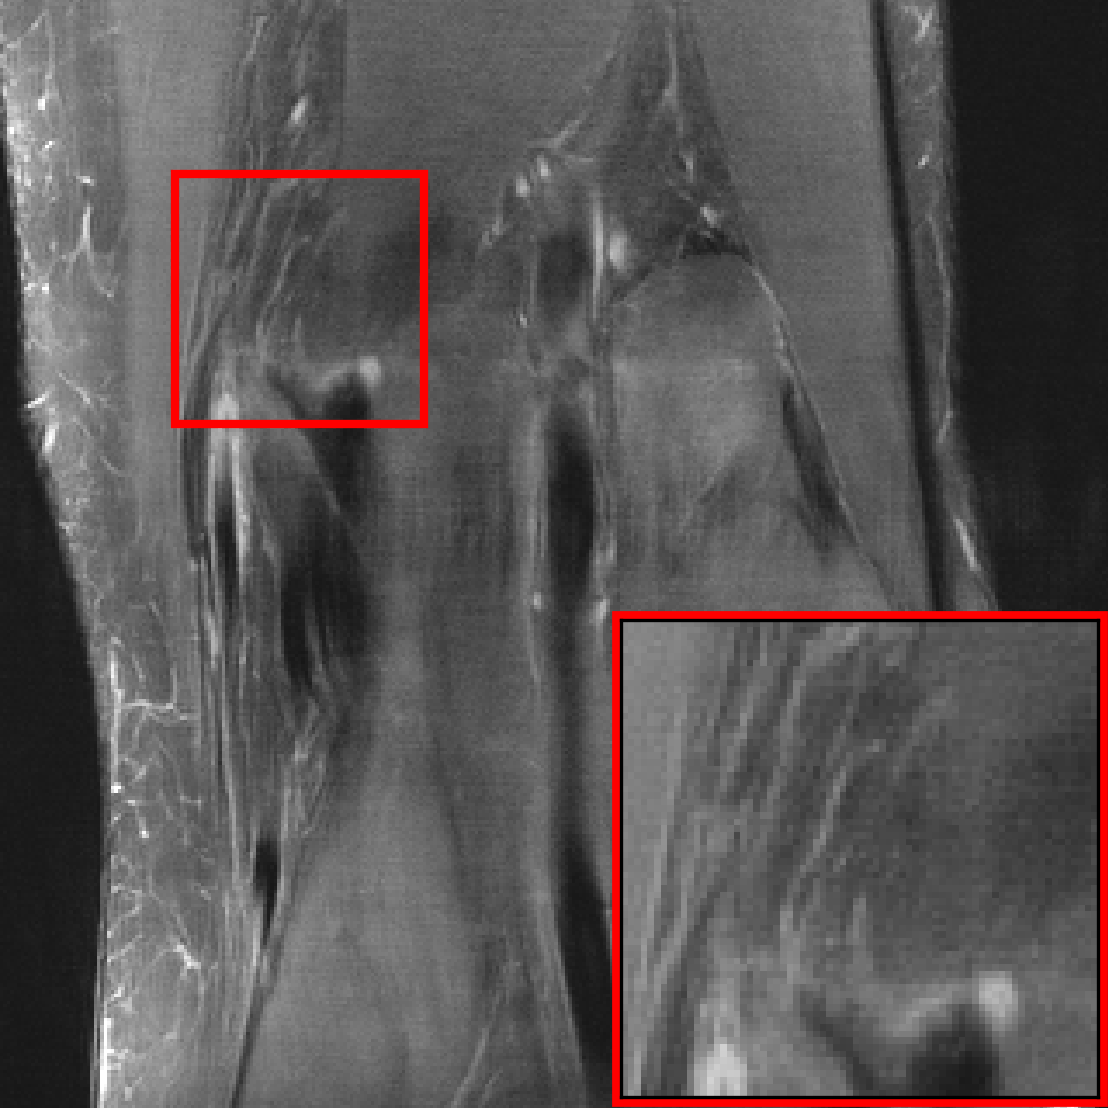

![[Uncaptioned image]](extracted/5298803/figs/pathology/lacunar_infarct_out_varnet.png)

![[Uncaptioned image]](extracted/5298803/figs/pathology/mass_out_varnet.png)

![[Uncaptioned image]](extracted/5298803/figs/pathology/lacunar_infarct_out_varnet_bl.png)

![[Uncaptioned image]](extracted/5298803/figs/pathology/mass_out_varnet_bl.png)

![[Uncaptioned image]](extracted/5298803/figs/pathology/lacunar_infarct_ref.png)

![[Uncaptioned image]](extracted/5298803/figs/pathology/mass_ref.png)

In this section, we investigate the distribution shift from healthy to non-healthy subjects by measuring how well models reconstruct images containing a pathology if no pathologies are contained in the training set. We find that models trained on fastMRI data without pathologies reconstruct fastMRI data with pathologies equally well as the same models trained on fastMRI data with pathologies.

We see that the models trained on show essentially the same performance (SSIM) as models trained on regardless of pathology size. The results indicate that models trained on images without pathologies can reconstruct pathologies as accurately as models trained on images with pathologies. This is further illustrated in Figure 6 (and Figure 16), where we show reconstructions given by the VarNet of images with a pathology: the model recovers the pathology well even though no pathologies are in the training set. Figure 14 in the appendix provides a more nuanced evaluation of the SSIM values for VarNet.